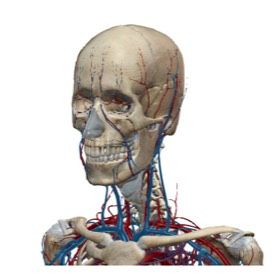

VENA JUGULAR

Ayat diatas merujuk secara langsung kepada salah satu urat yang penting dalam sistem peredaran darah iaitu urat leher atau “jugular vein” yang menjadi sebahagian dari rangkaian vena yang berfungsi membawa darah yang mengandungi kabon dioksida kembali kejantung untuk disegarkan semula dengan oksigen dalam proses pernafasan di paru-paru.

Setelah AlQuran menyentuh URAT VENA, Allah SWT melengkapakan sistem peredaran darah dengan menyentuh satu lagi urat utama iaitu ARTERI yang menjadi sebahagian dari rangkaian utama yang disebut AORTA pada ayat 44-46 dari surah yang ke69 AlHaqqah.

Perkataan “Al-Watin” pada ayat ini telah diterjemahkan kepada beberapa makna yang kesemuanya terjurus pada maksud yang sama iaitu “AORTA”, yang merupakan “nadi kehidupan”. Disini kita dimaklumkan oleh Allah SWT akan fungsinya aorta dan rangkaian arteri yang menjana kehidupan manusia kerana sekiranya terputus rangkaian ini maka kematian akan menyusul hampir dengan serta-merta.

Mari kita teliti bentuk organ Jantung pada gambar sisipan. Kita akan dapati ada tiga cabang pada aorta sejurus selepas meninggalkan jantung. Sekiranya kita bayangkan jantung sebagai pusat rezeki dan peredaran darah sebagai sebuah kenderaan, persimpangan pertama yang akan dilalui oleh kenderaan darah ini ialah bahagian kepala dan juga kedua belah “sayap’ tubuh yang merangkumi bahu dan kedua belah tangan yang disebut dalam istilah anatomy sebagai "UPPER EXTREMITIES"